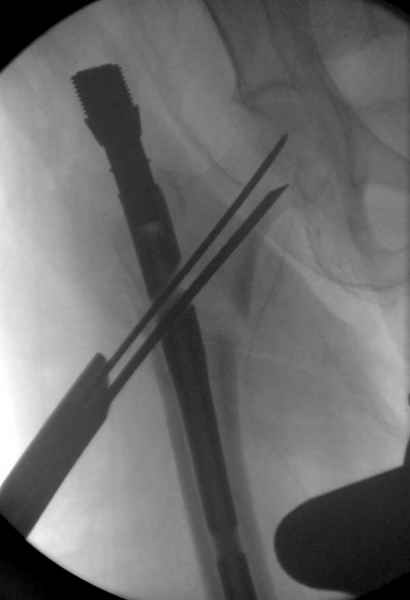

Изначально была выбрана не правильная точка введения стержня, в связи с чем в конце, я подчеркну, в конце операции произошло из-за напряжения между прокимальным концом канала бедра и стержнем разрушение в/3 бедра.

Проволока наложена потому, что при введении штифта не прошли эту зону римером и произошли сколы на концах отломков.

Под ЭОП во время операции такого смещения не было. Мы бы конечно не отпустили этого больного с такой картиной (сами бы что-то сделали или к вам отпр).